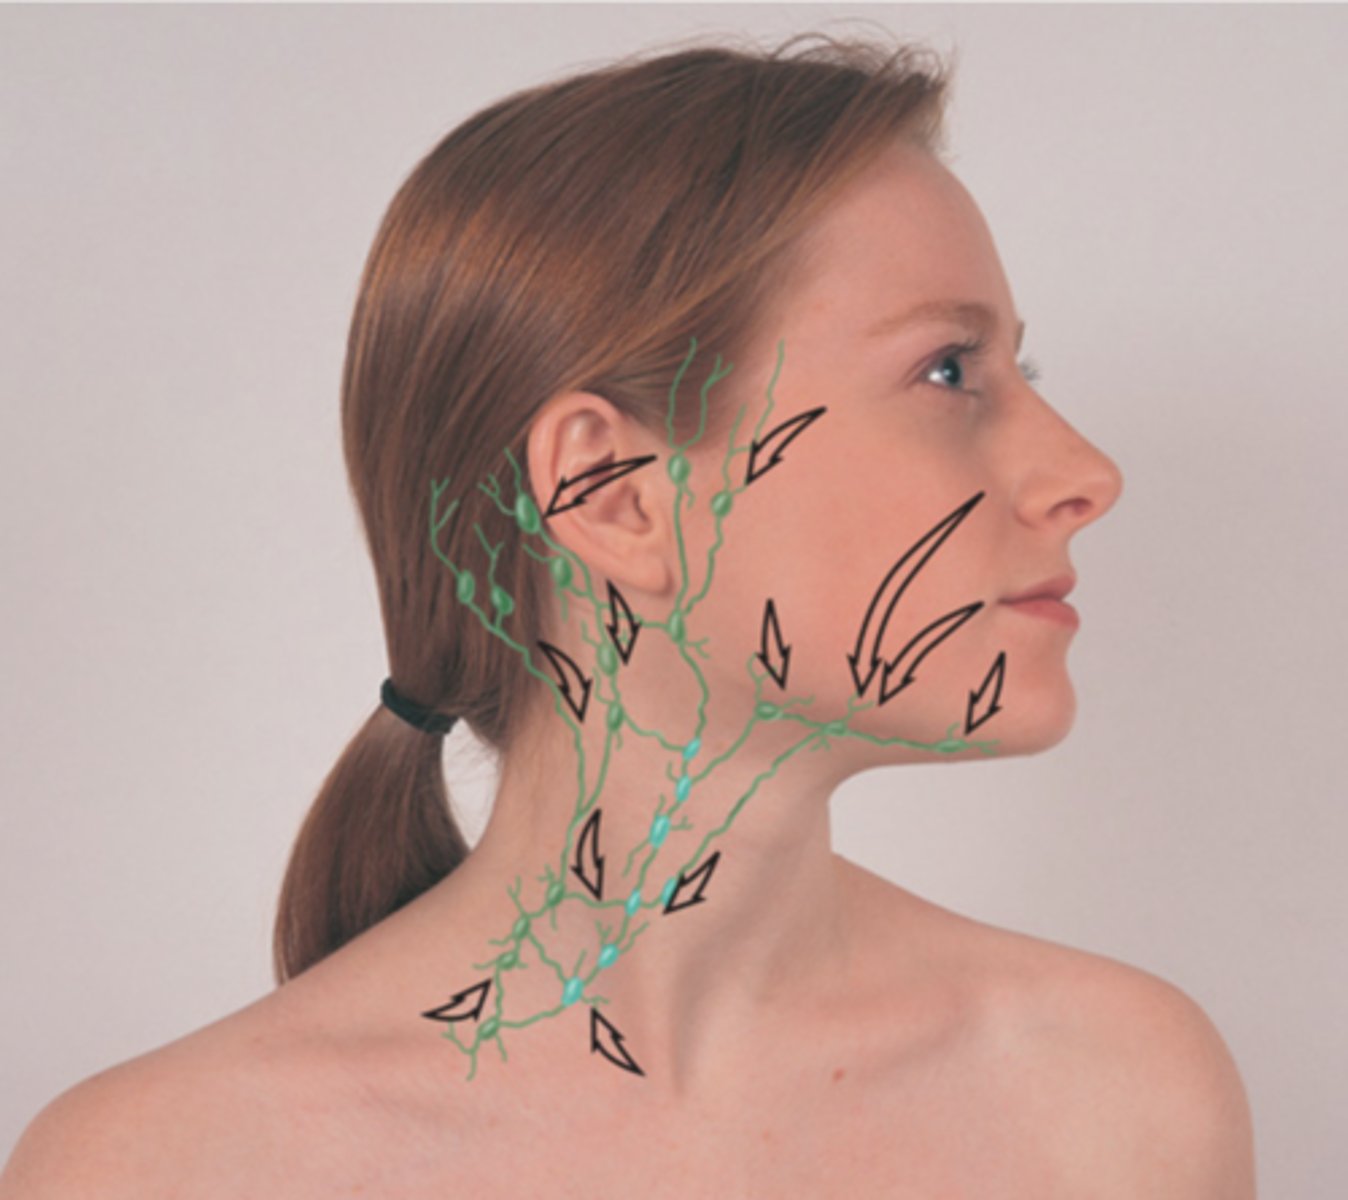

Major Lymph Nodes in the Neck (FUN!)

(Party People Often Sell Sardines Just So Dogs Pee Silver)

Functions of the Lymphatic System

- Manages interstitial fluid

- Part of the immune system

- Absorbs fat from the gut

Key Points on Head, Face, and Neck

- Inspection and palpation are key

- State the names of the lymph nodes as you palpate them